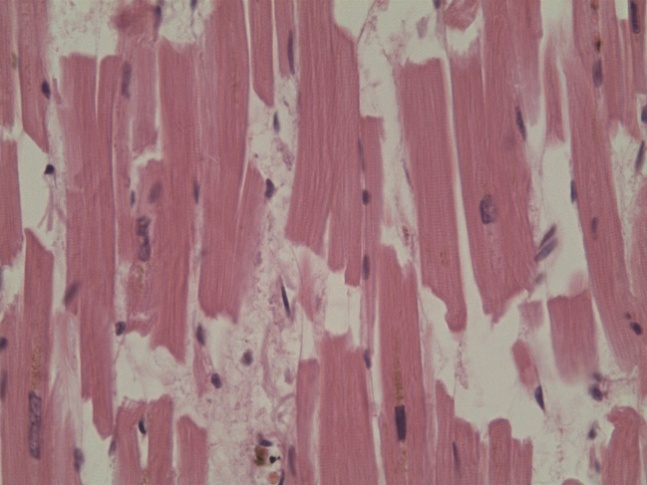

Сердце (рис. 3): в миокарде выявлены контрактурные изменения кардиомиоцитов, множественные мелкие рубцы, преимущественно вокруг артерий, выраженный отек стромы, полнокровие и эритродиапедез.

Рис. 3. Фрагментация кардиомиоцитов. Гематоксилин и эозин. Ув.х200